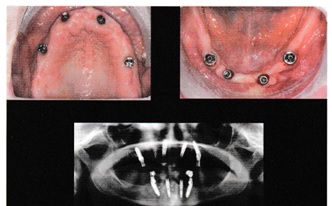

A fotókon jól láthatóak a páciens által jelzett problémák, különösen az ívekben lévő fogakhoz kapcsolódó csontvesztés előrehaladott állapota (1, 2. ábra).

A harmadik látogatáskor elvégeztük a műtéti fázist a belső hatszögletű implantátumok (AoN Cyroth, Vicenza) 30 Ncm és 60 Ncm közötti forgatónyomatékkal történt behelyezésével.

A hátsó szektorokban, ahol a dőlésszög meghaladta a 30°-ot a behelyezési tengelyhez képest (a NAI vagy a sinus maxillaris szintjén), úgy döntöttünk, hogy az implantátum gyártó multiunit felépítményeit alkalmazzuk a csavarlyuk középponti elhelyezésére a fog centrális barázdájában, míg elöl, ahol a hajlásszögek kisebbek voltak, mint 10°, a konometrikus protézisekhez való pilléreket használtak, amelyek egymással párhuzamosan helyezkedtek el. Az alkatrészek összeszerelése 25 Ncm-es nyomatékkal történt. A 42es pozícióban lévő implantátum közelében a csontprofilt kollagén felszívódó membránnal (Bioteck, Vicenza) és szintetikus csontrészecskékkel (Perioglas, Novabone products, Alachua, USA) állítottuk helyre, hogy elérjük a nyálkahártya megfelelő kiemelkedését és a problémás alámenősség elkerülhető legyen (3. ábra)